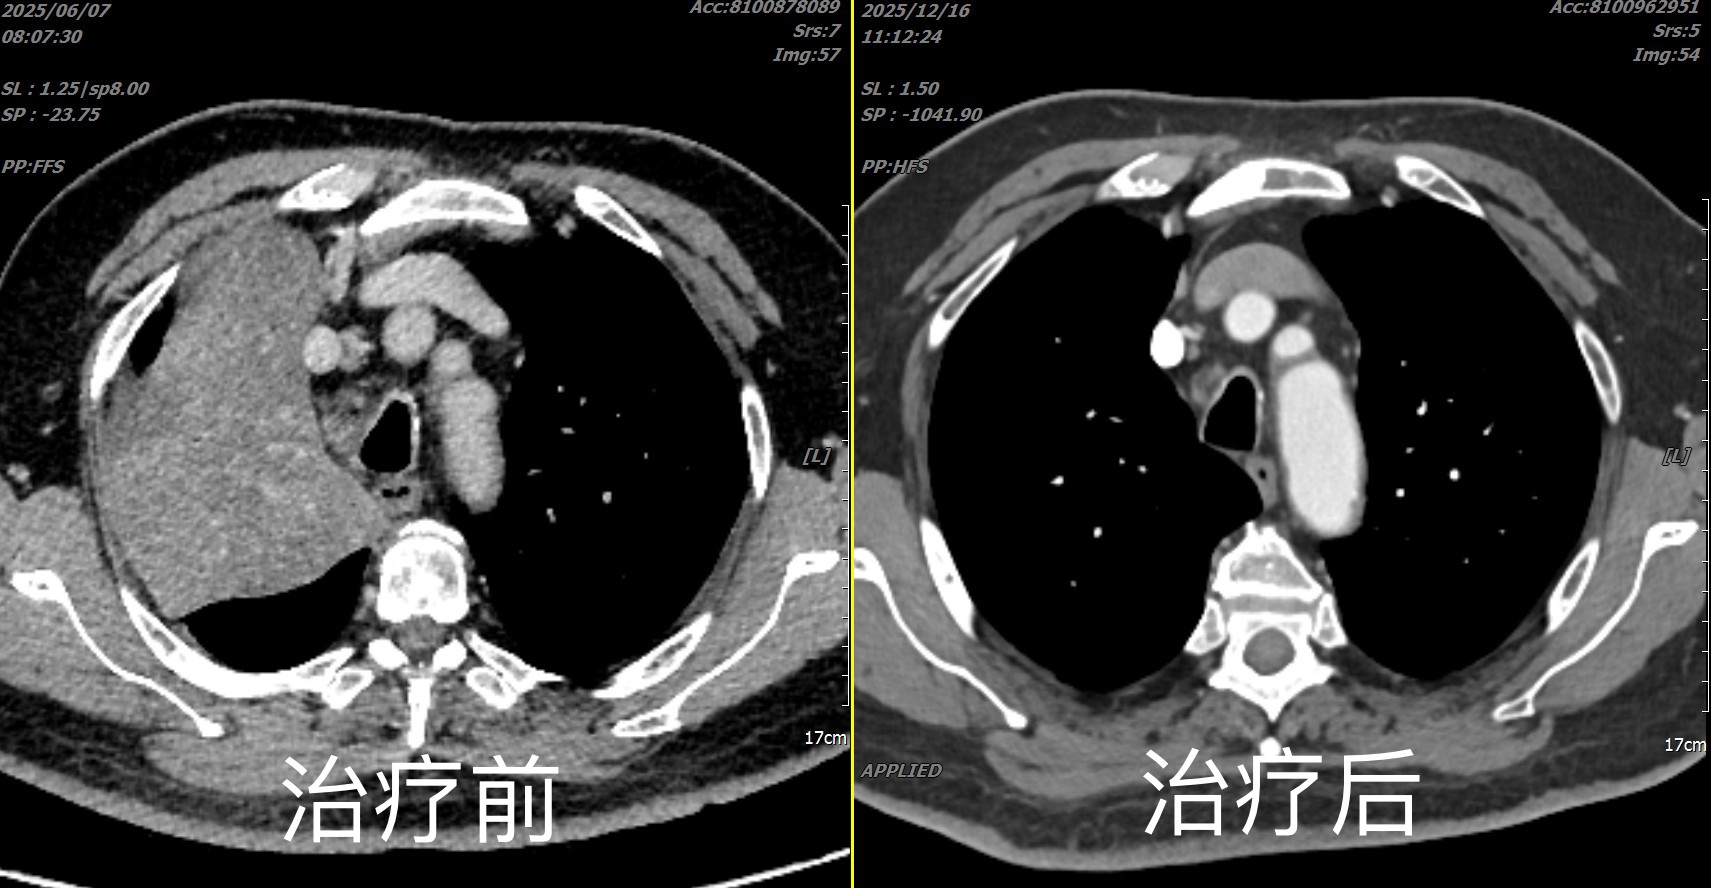

病例一:肺癌精准分期,避免过度治疗

一位老年男性患者,因咳嗽、气短入院,CT发现肺部肿块并伴有纵隔多发淋巴结肿大。传统检查难以判断淋巴结是炎症还是癌转移。

经我科超声支气管镜检查,在超声实时引导下,对多个可疑淋巴结进行了安全、精准的穿刺活检。病理结果证实部分淋巴结为转移癌,明确了肺癌分期为III期。这一关键诊断,使患者避免了直接手术(若淋巴结为阴性可手术),转而接受了更合适的新辅助化疗联合免疫治疗,为制定科学、个性化的治疗方案提供了决定性依据。